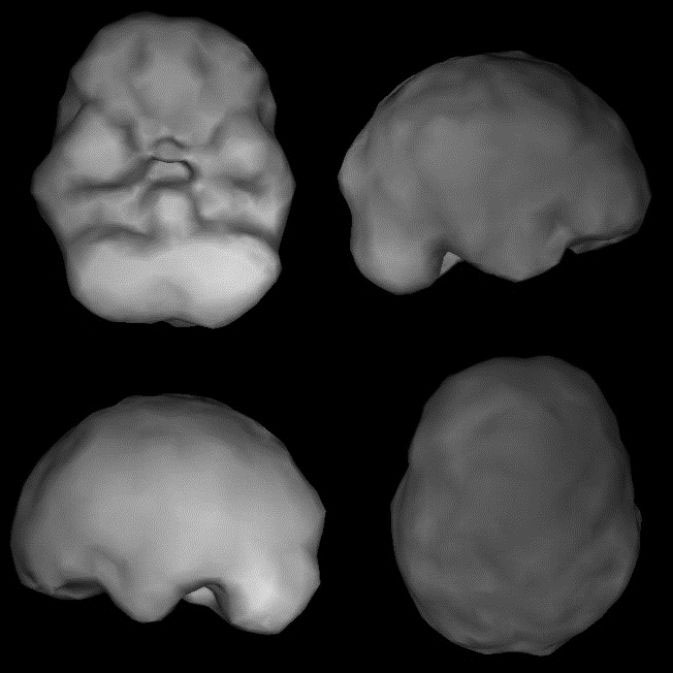

Я познакомился со Стивеном после того, как работал с его женой, актрисой и комиком Лорой Клери. Она обратилась к нам в связи с проблемами с концентрацией внимания, тревогой и мрачными мыслями. Лора сняла свое обследование у меня и выложила несколько видео в Интернет, где они набрали более 10 миллионов просмотров. В рамках обследования Стивена мы собрали подробный анамнез, чтобы понять историю его жизни, провели полный набор лабораторных анализов и сделали ОФЭКТ. Ниже представлен скан ОФЭКТ здорового мозга, на котором видно ровную и симметричную активность.

Офэкт-снимок здоровой поверхности мозга

Сверху слева: вид мозга снизу. Сверху справа: вид мозга с правой стороны. Снизу слева: вид мозга с левой стороны. Снизу справа: вид мозга сверху. Здоровый = гладкая, ровная, симметричная активность

Офэкт-снимок поверхности мозга Стивена

Сверху слева: отверстия показывают низкий кровоток в префронтальной коре и правой височной доле. Сверху справа и снизу слева: уменьшение левой и правой затылочных долей

ОФЭКТ-сканирование мозга Стивена показало явные признаки пережитой травмы головы с низким кровотоком в правой префронтальной коре, правой височной доле, а также левой и правой затылочных долях. При обсуждении он подтвердил, что, когда был маленьким, как-то свалился с лестничного пролета, потеряв сознание.

Может ли падение в детстве привести к тому, что вся жизнь будет наполнена грустью? Несомненно. Недиагностированные повреждения мозга – один из ключевых факторов депрессии, тревожности, СДВГ, зависимостей, ощущения безнадежности и самоубийств. Несмотря на походы к психиатрам, психологам и другим специалистам, никто не изучал историю мозга Стивена, ведь никто и не смотрел на его мозг. Всего два месяца фототерапии для его мозга, приема подходящих его типу мозга нутрицевтиков и сознательного умения дистанцироваться от плохих мыслей, забредающих ему в голову, и Стивен начал чувствовать себя куда счастливее. У него появилась надежда, и он начал контролировать свои эмоции.